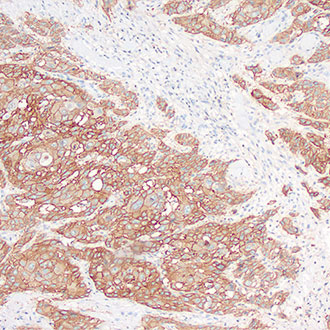

EGFR

EGFR -